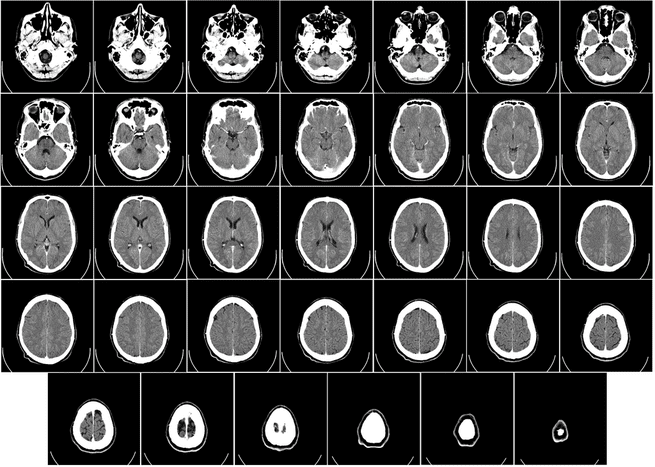

ربما يكون التطور الذي أتى في السبعينيات هو الأهم، مع ظهور أول آلة تصوير مقطعي محوسب بالأشعة السينية، أو ماسح سي تي. وباستخدام الحساسات لتحديد خرج الأشعة السينية التي تخترق جسد المريض، تقوم الآلة بتركيب صور دقيقة للعظام، والأعضاء، والنسج اللينة في نفس الوقت. ونظراً لاختلاف درجة اختراق الأشعة لكل مادة في جسد المريض، يمكن للآلة أن تميز بنجاح ما بين الذراع والطحال، وترسم الاثنين بدقة. يقول بانيرجي: "يعتبر هذا أحدث التطبيقات العصرية للأشعة السينية".

إن تعديل التيار الأنبوبي في آلة التصوير المقطعي يعني أن جرعة الأشعة تتغير وفقاً للجزء من الجسم الذي يتم تعريضه لها. وفي عمليات المسح الكامل للجسم، يتم إطلاق الأشعة إلى الجمجمة الصلبة بمقدار أكبر من الأشعة المستخدمة للرئتين المليئتين بالهواء، ما يسمح بمرونة أكبر في التعامل مع وقت التعرض الكلي. أما إعادة التشكيل التكرارية فهي العملية التي تقوم بها خوارزمية في آلة التصوير المقطعي بتجميع صور عالية الدقة للجسم، وبتخفيض الضجيج وتوضيح الصورة، يمكن للمريض أن يقلل من الوقت الذي يقضيه تحت تأثير الإشعاع في هذه الآلة الضخمة الشبيهة بالكعكة المحلاة.